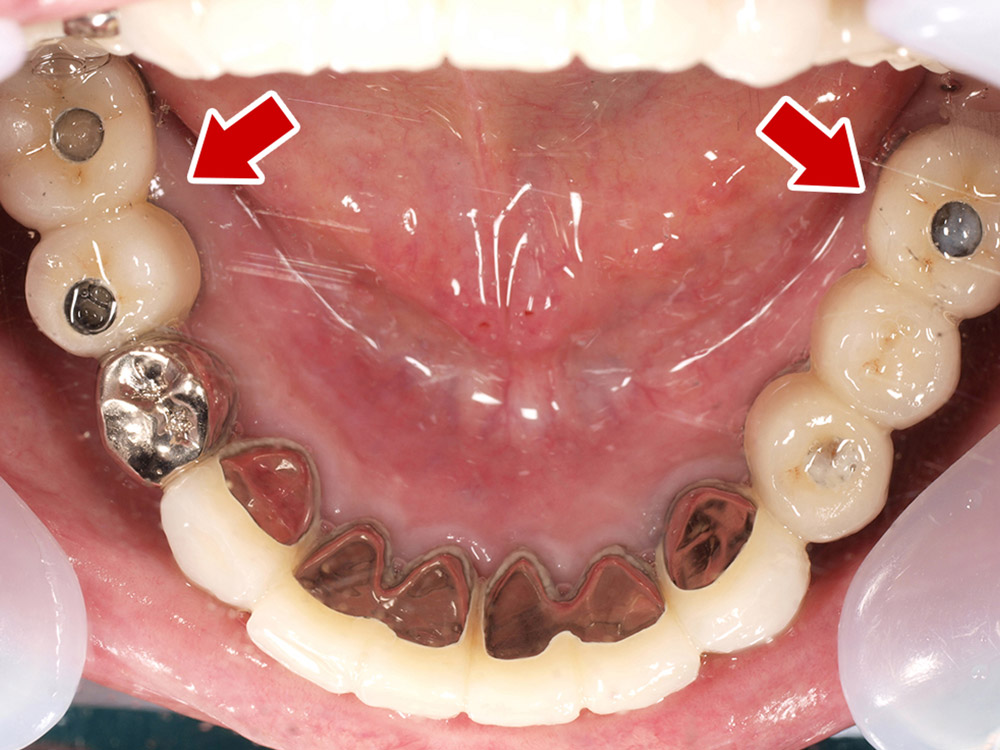

- 主訴

- 入れ歯が気持ち悪く、しっかりと食べれない。本当につらい。美味しく食べて、豊かな人生を過ごしたい。

- 処置内容

- 上顎6本(オールオン6)

- 治療費用

- 上顎350万円(税込)

- 治療期間

- 上顎1年(仮歯まで8か月)/約10回

- リスク

- 上部構造物、仮歯の破折、術後の腫れ(3日)、人工歯根脱落のリスクがあります